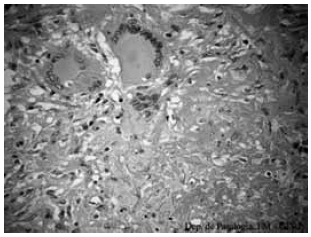

Considere a imagem:

A presente morfologia corresponde à